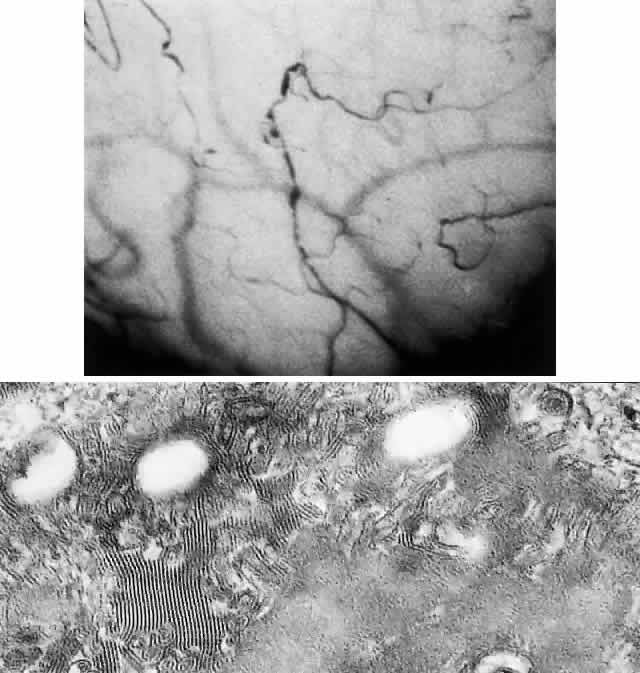

Cornea. Whorl-like corneal opacities (Fig. 15) are seen in almost all homozygotes and heterozygotes, with more severe involvement in heterozygotes.159 In female carriers, these corneal changes are usually the only manifestations of the disorder. They occur primarily in the subepithelial layers of the cornea, at or near the level of Bowman's layer. These linelike opacities are made up of a multitude of small dots, usually in the cornea. They are mostly cream-colored but range from white to golden brown. The corneal dystrophy (cornea verticillata) appears in a number of patterns. The more fully developed vortex patterns also involve the upper cornea. Lesions appear as a diffuse haze in younger patients and may be seen as early as 6 months of age.161 Corneal dystrophy does not impair visual acuity.159,160 Conjunctival inclusion tortuosities, isolated dilation or saccular aneurysms, as well as sheathing, may be present (Fig. 16).

Fig. 16. Fabry's disease. Top, Tortuosity and aneurysmal conjunctival dilatations. Bottom, Conjunctival biopsy shows inclusions within capillary endothelial cells as parallel leaflets. (× 80,000.) (Courtesy of Drs. Kenneth Kenyon and Jacques Libert)

Lens. Two specific types of lenticular changes may be seen: a granular, anterior capsular cataract with a radial pattern and an unusual posterior subcapsular cataract with whitish, translucent spokelike deposits of granular material radiating from the central part of the posterior cortex.